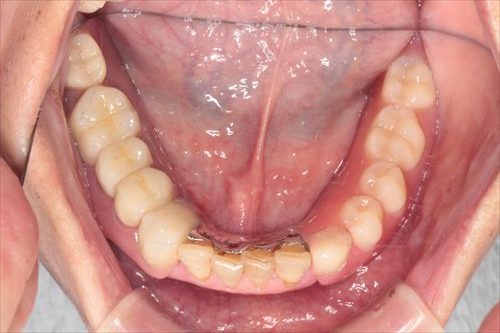

義歯を外したところです。

上下どちらの顎も、歯の無い部分が大きくえぐれているのがわかるでしょうか?

これがすれ違い咬合の怖さです。残っている歯による顎の骨への攻撃が強いため、顎の骨が経年的に失われていきます。